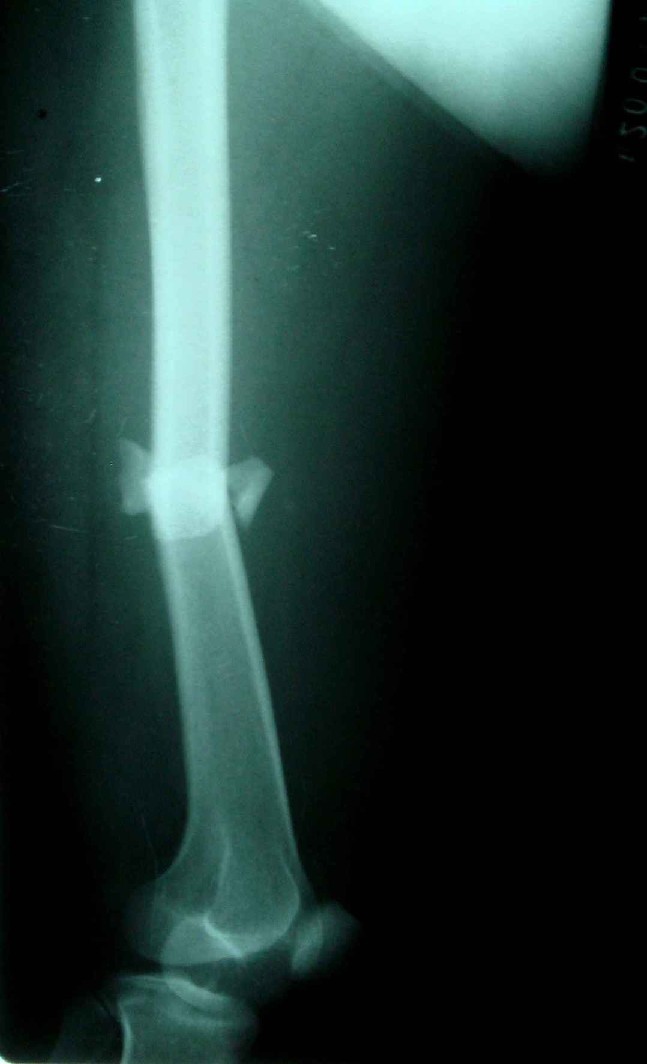

患者,女,因外伤就诊。摄骨盆及右股骨。当时报告骨盆未见明显异常,右股骨中段粉碎性骨折。五天后行股骨中段骨折内固定手术,术中摄床边片示股骨颈骨折。现把术前和术中图像上传。请大家高诊,分析股骨颈骨折是术前漏诊还是其他原因。术前骨盆片右股骨颈显示欠佳是由于股骨中段骨折无法将股骨颈完全显示。

现在我向大家请教,股骨中段粉碎性骨折的同时股骨颈也会骨折吗,另外如图所示该患者股骨颈骨折线是我们常见的由外伤引起的骨折线吗。

关于楼主说的骨折线的形态,的确和一般外伤的有种不太一样的感觉,上方裂隙较明显,下方骨皮质“连续”,我认为成年人应该是全部断了的,不全骨折的可能性非常非常小,该片恰好无法全部显示骨折线。骨折线的形态不能判定术前还是术后骨折。以上只是个人小小看法,请各位老师指正为谢!